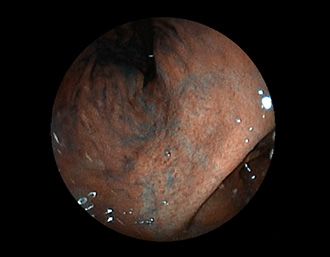

症例3:十二指腸潰瘍(53才男性)

1年前からの慢性胃痛を主訴に当院受診。十二指腸球部前壁に深くて大きな潰瘍(Stage A1)があり、潰瘍底は厚い白苔に覆われ、一部白苔のはみ出しを認める。潰瘍周囲粘膜は浮腫を伴っている。ボノプラザンフマル酸塩投薬で治療開始しました。

(通常画像)